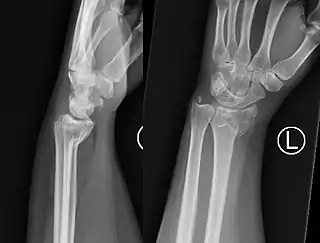

![]() Fractura de Smith muñeca izquierda | ||

La fractura de Goyrand-Smith o fractura de Smith (o fractura de Colles invertida) es una fractura del extremo distal del radio con desplazamiento palmar del fragmento y la mano, respecto del radio; esto produce la deformidad en pala de jardinería. Su epónimo se debe al médico, cirujano y político francés Gaspard Goyrand[1] y al cirujano ortopédico irlandés Robert William Smith que la describe en su obra Treatise on Fractures in the Vicinity of Joints, and on certain forms of Accidents and Congenital Dislocations, publicada en 1847.[2]

El fragmento de fractura distal se desplaza de forma volar (ventralmente), a diferencia de la fractura de Colles, que el fragmento se desplaza dorsalmente. Dependiendo de la gravedad del impacto, puede haber uno o varios fragmentos y puede o no afectar la superficie articular de la articulación de la muñeca.

El diagnóstico inicial es clínico mediante al exploración, haciendonos sospechar la presencia de este tipo de fractura si se presentan los signos detallados arriba. Ante esta sospecha, el diagnóstico final apropiado de este tipo de fracturas necesita la realización de una radiografía simple del antebrazo distal y del carpo en al menos dos proyecciones: antero-posterior y lateral. En algunos casos, una vez realizada la radiografía simple, cuando las imágenes muestren que se trata de una fractura multifragmentario o compleja, la realización de una tomografía computarizada simple de la lesión puede ser útil para guiar el tratamiento.